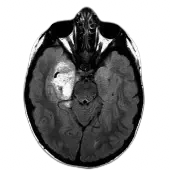

Unified Platform for All Modalities

Copilot brings AI radiology capabilities to all imaging modalities, ensuring consistent and efficient analysis.

CT

MRI